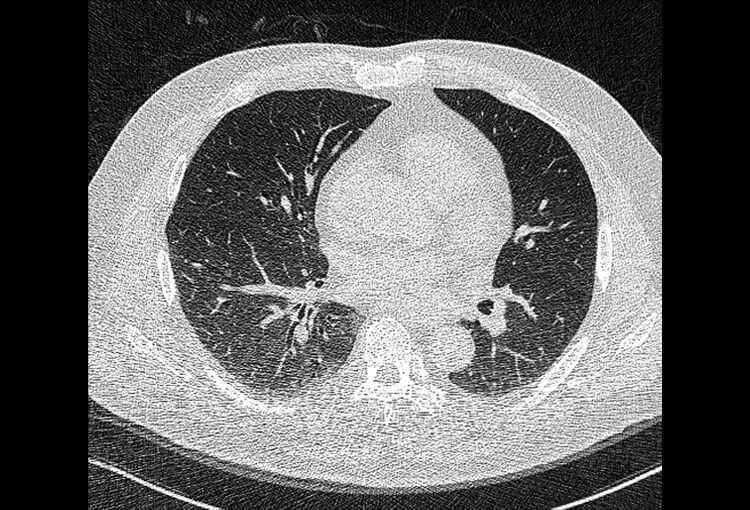

Before and After Denoising

120 kV / 30 mAs / 1mm

Before FBP (Noise 150) VS After ClariCT.AI (Noise 49) 67% Denoising